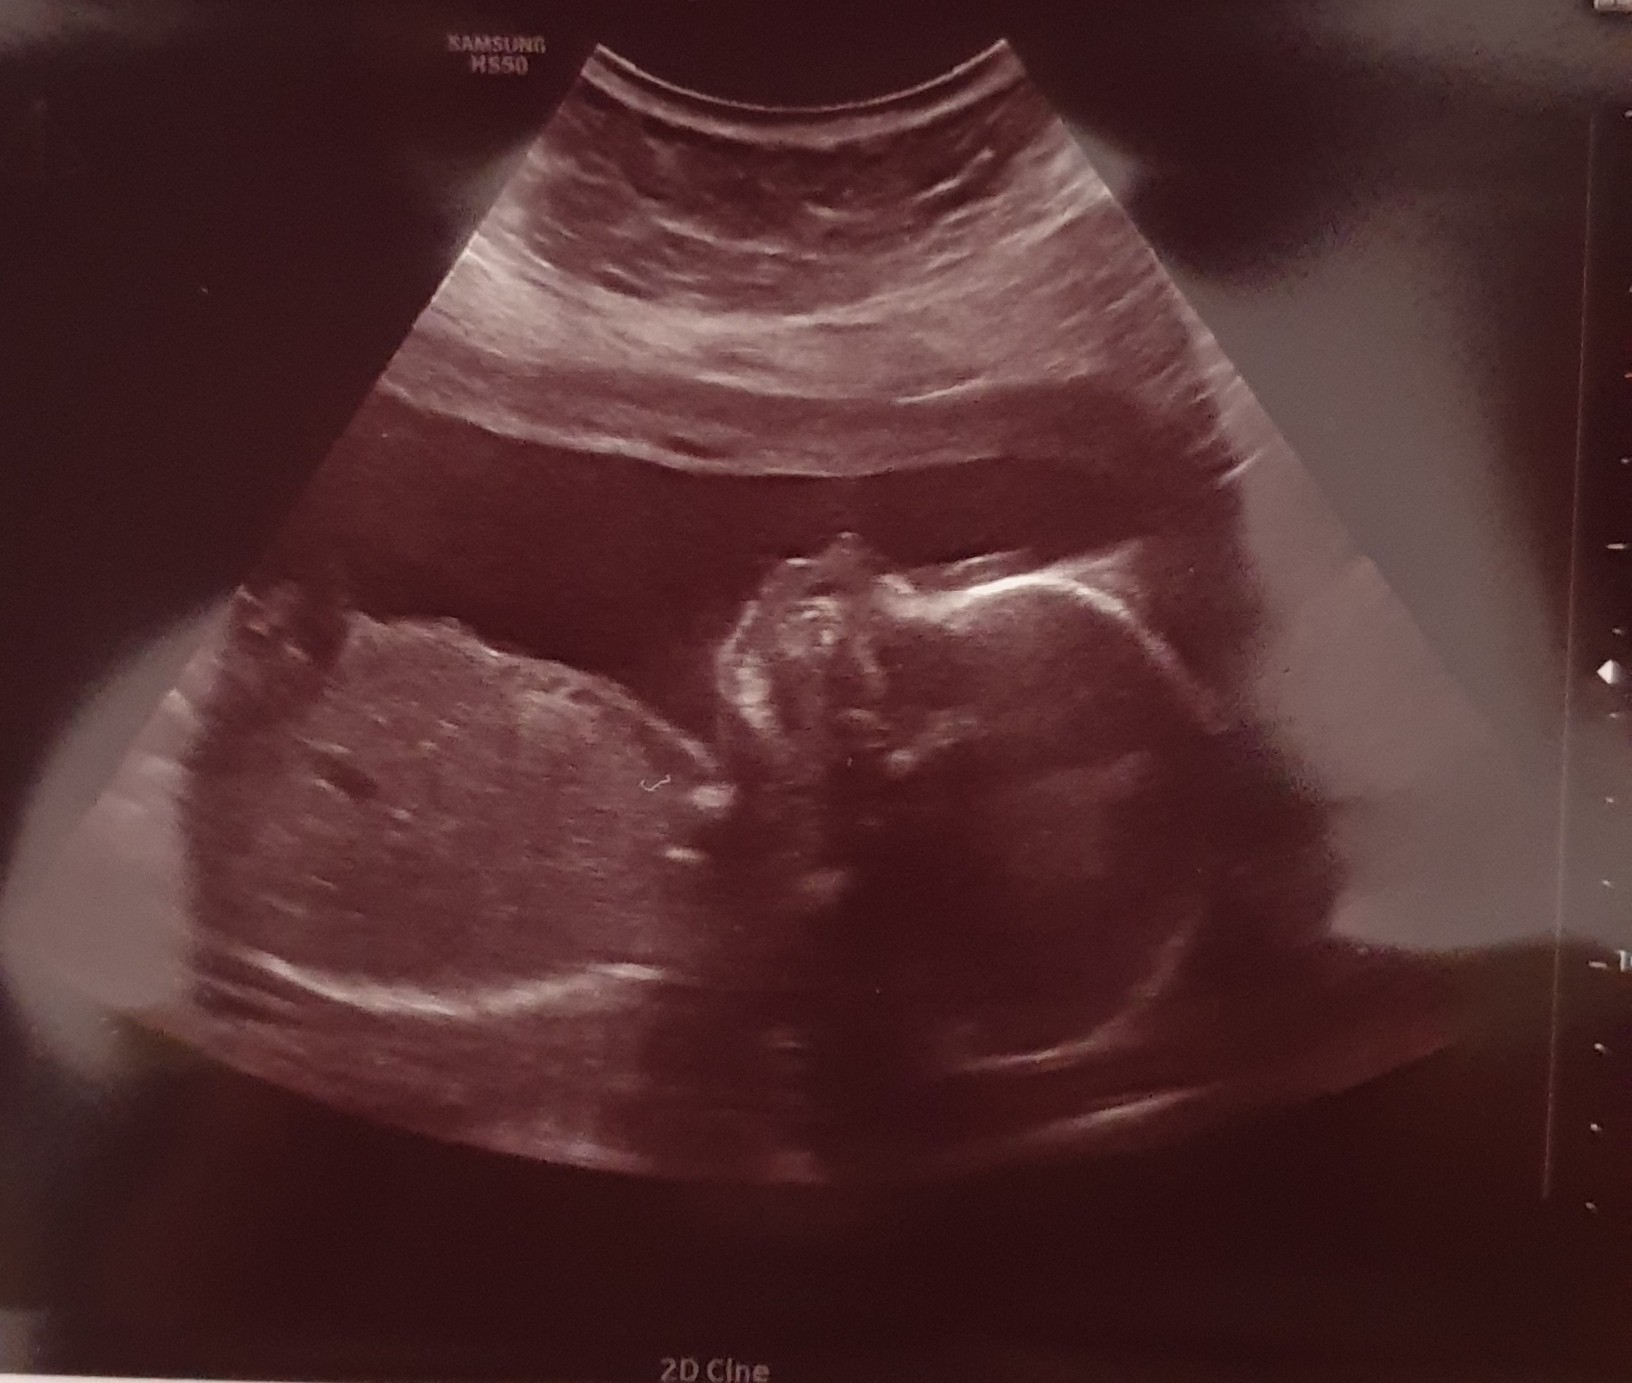

Pewnie dziewczynka.Bo wśród moich znajomych to właśnie córeczki długo się ukrywały i zazwyczaj były mniejszeJa po polowkowym. Dziecko młodsze o 1,5tyg wcześniej różnica była 2dni. Położenie miednicowe i dalej nie wiem czy chłop czy baba.

Czyli z tym młodszym jak u mnie.Ja po polowkowym. Dziecko młodsze o 1,5tyg wcześniej różnica była 2dni. Położenie miednicowe i dalej nie wiem czy chłop czy baba.